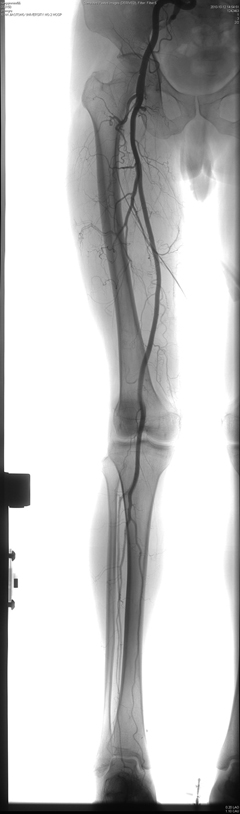

下肢血管造影无缝拼接

Innova4100拥有业界最大视野40×40cm,即标准的16英寸大视野,这就使得4100在做全腹部造影时可轻松覆盖全腹,在做血管跟踪造影时,与纵向移动达170cm的专用导管床配合,可一次完成从胸部到脚的双侧血管跟踪造影,从而有效减少了球管曝光次数,缩短了手术时间,极大降低病人受辐射剂量。

除了实时DSA,路径图,QVA等常规介入软件外,还将支持Fastspin高速旋转DSA, Bolus chasing下肢血管连续跟踪造影和无缝拼接等高级功能软件,尤其令临床医生振奋的是将支持代表目前血管造影机最高软件水平的3D路径图,Innova3D和InnovaCT。3D路径图与普通路径图相比能更准确地反映血管的真实走向,大大缩短手术时间和难度,对于超选插管等复杂手术具有重大的指导意义。Innova3D可以显示从软组织,骨头和血管的不同断面的图像,一方面可以显示更精确的三维血管图像,而且还可以显示血管与软组织,骨组织之间的关系,可用于血管和其他小部位如脊柱和眼眶的血管和骨头能更精确的观察。而业界独有的InnovaCT更是最高软硬件技术的完美结合,它融合了CT和DSA图像特点,对于疾病诊断和手术计划的制定等方面有很大的用处:如可以用来评估肿瘤的来源, TACE手术血流动力学观察,TACE术后效果判断,肿瘤早期诊断,器官移植的血供分析,脊椎疼痛治疗以及脑神经手术中脑出血诊断等复杂手术。Bolus chasing下肢血管连续跟踪造影和无缝拼接可以实现一次造影就可以全程显示下肢血管。另外其基于3D技术的血管仿真内窥镜技术可以显示血管腔内的结构,为介入诊断治疗提供参考。(影像科 祁晓江/文 张雷 祁晓江/图)